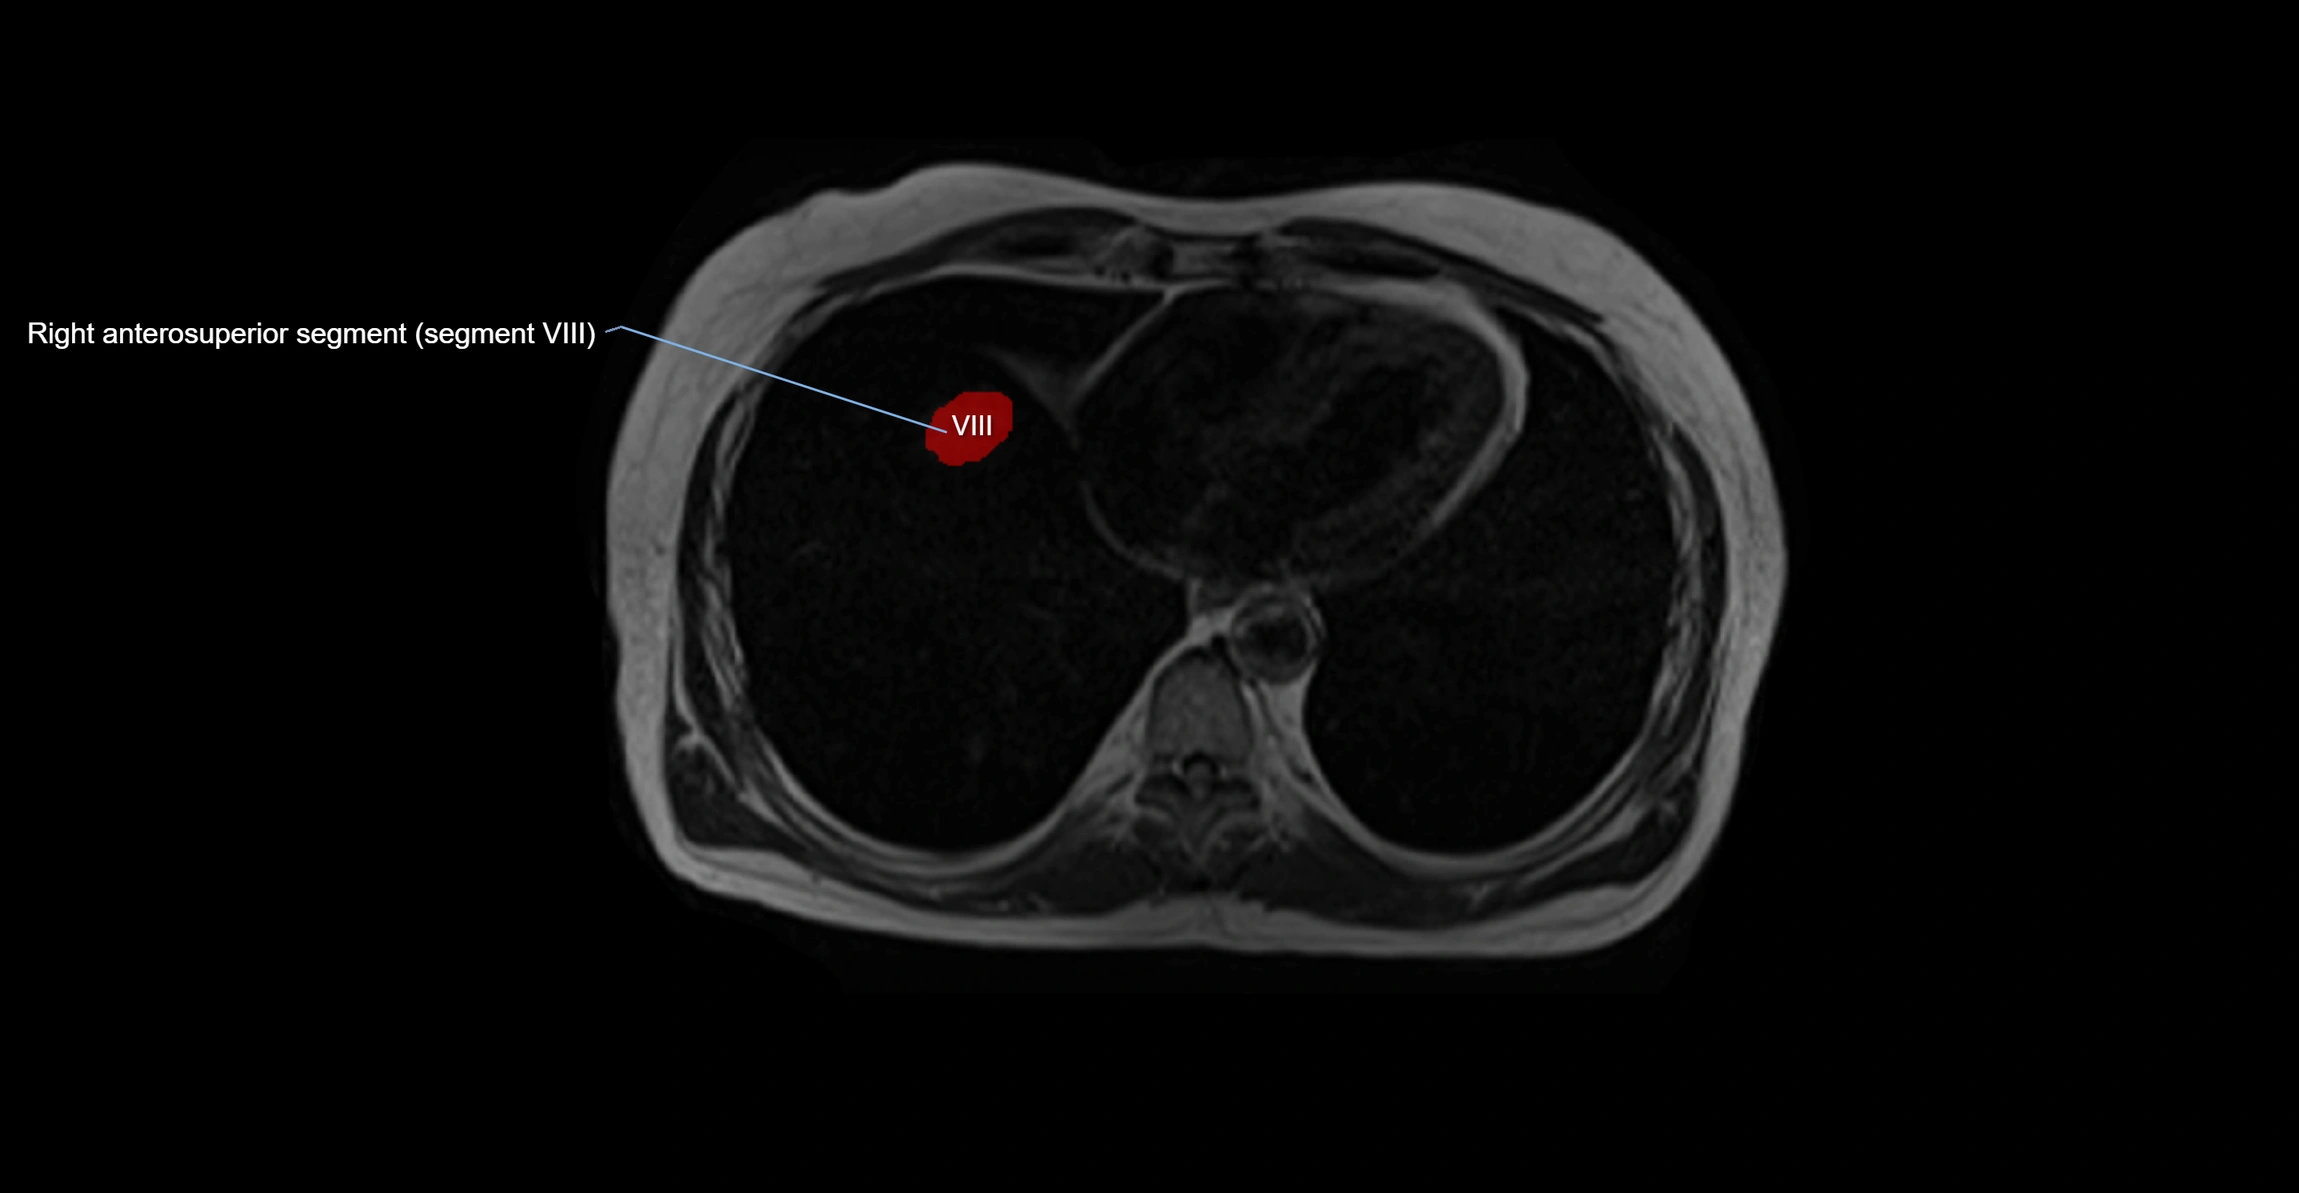

MRI image